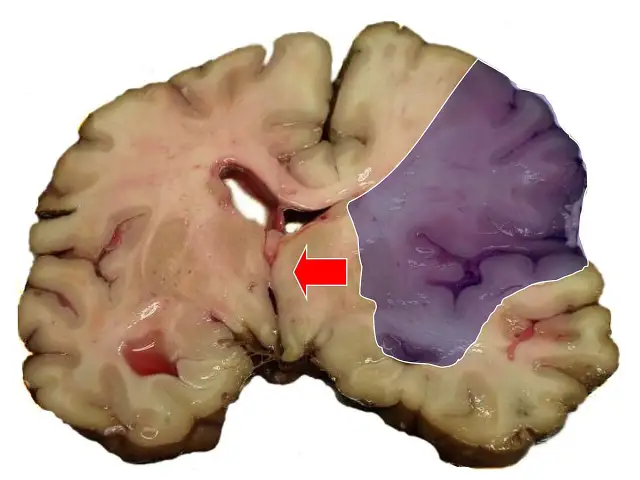

Udar czy wylew? Rozwiej wątpliwości! Poznaj różnice, objawy (U.D.A.R.), pierwszą pomoc i profilaktykę. Sprawdź, jak ratować życie!

Udar a wylew czy to to samo? Poznaj kluczowe różnice między udarem niedokrwiennym a krwotocznym. Dowiedz się, jak rozpoznać objawy (FAST) i dlaczego szybka reakcja ratuje życie. Przeczytaj!